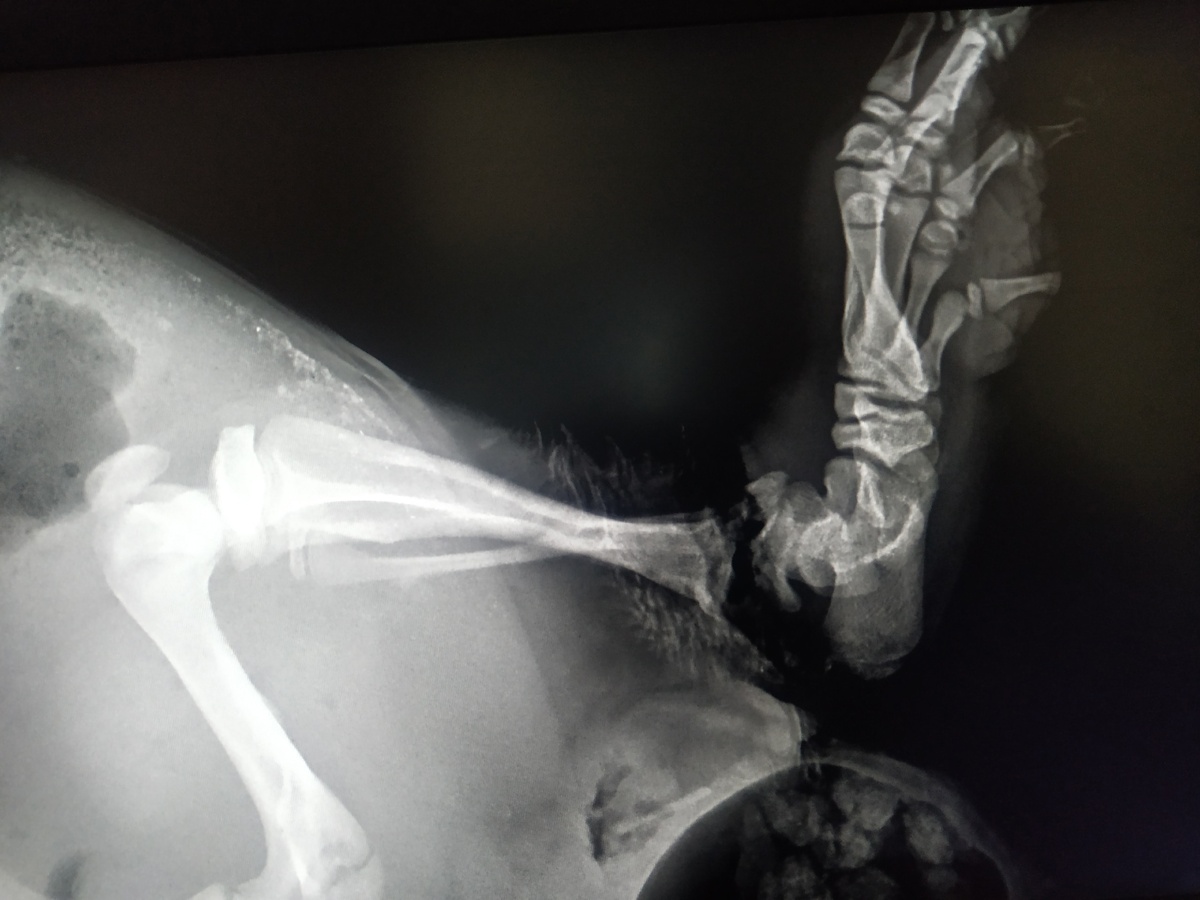

Ну, и четвертое и самое печальное – лапу перебило наглухо, кости уже не срастутся, конечность придется ампутировать.

— Лапа перебита полностью, бобрика ждет ампутация, — с сожалением сообщают волонтеры на своих ресурсах и делятся новыми снимками (в том числе и рентгеновскими).